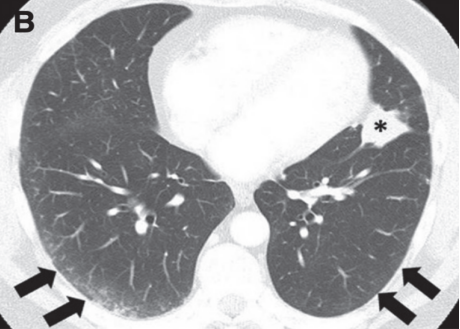

(2)隐源性机化性肺炎(COP):是NSCLC中最常见的CIP类型,双侧多灶性实变,周围和下肺分布,伴有GGO和网状阴影[17]

图片

还可以表现为机化性肺炎(OP),反向环礁或晕征,被认为是CIP中OP的相对特殊特征[18]